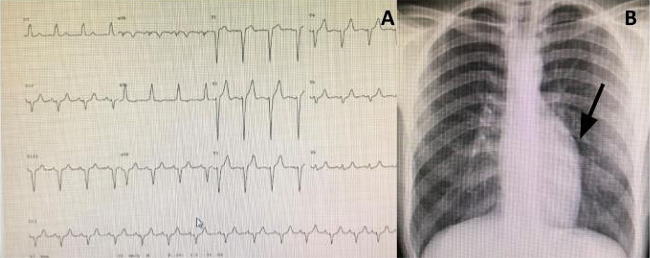

Electrocardiogram: Frequent findings include a q wave in V1 and inferior leads with absent q wave in V6 (Figure 1A). However, this is not the case for all patients. Complete heart block is also seen, may be found incidentally or in symptomatic patients, and may be the first clue to diagnosis[13].

Chest radiography: The so-called “humped appearance” of the left border (Figure 1B, arrow), is common but not always present. Variations in heart shape can be found, depending on the presence and severity of the associated lesions as well as on the degree of heart dysfunction[17].